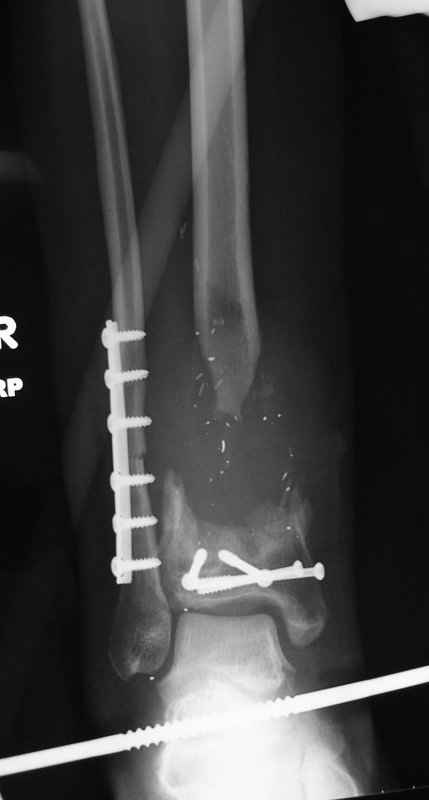

5. Ну и чтобы не быть голословным. Молодой человек подорвался на фугасе (Чечня, 2005 год). Свежие рентгенограммы:

Соответственно ожоги и дефект мягких тканей, переломы костей стопы и пр. Наложили аппарат

Илизарова (как придется), хирургически обработали и героически заживляли мягкие ткани с многочисленными кожными пластиками. В итоге через полгода я принял его вот таким:

Реализовал описанную выше методику, и в итоге вот что получилось. Высылаю лишь прямые проекции,

в боковых тоже всё в тему.

Очень пригодились карбоновые кольца (Джолдас -огромное спасибо, я твой должник!!!), поскольку остеопороз дистального отломка был просто невероятный. На цифровом рентгене с трудом угадывались контуры.

Рентген в процессе перемещения - внизу карбоновые кольца, тракция фрагмента спицами с упором.

внешний вид в аппарате - не завершающем этапе, сначала стопа тоже была фиксирована в аппарате.

Сейчас аппарат сняли, но случай ещё не завершенный.

Признаюсь честно, не совсем уверен в прочности консолидации на стыке косточек. Кроме того, укорочение в районе 6 см. Сейчас реабилитация - ходит опираясь на ногу с одним костылем.

Продолжение, видимо, будет... Возможно, будем удлинять.